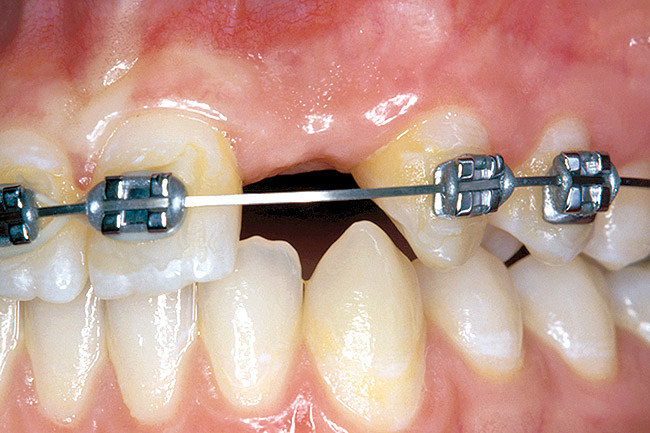

Congenitally Missing Laterals

A 17-year-old boy presented with a history of congenitally missing maxillary lateral incisors. The patient had been under the care of an orthodontist for several years to manage his occlusion during his adolescent growth phase. The patient originally presented with his parents after being told that the “braces were ready to be removed, and their son was now ready for implants to replace the missing teeth.” This is not an uncommon circumstance, and unfortunately the orthodontic alignment was performed before the patient was sent to the restoring dentist. Therefore, the orthodontist was not aware of the space requirements for future implant placement. This case highlights the importance of proper communication between all members of the implant team, especially during the orthodontic planning phase. The patient’s medical history was unremarkable, and the patient was found to be healthy and a good potential candidate for dental implants to replace the missing lateral incisors.

Periapical radiographs were taken to help determine the mesial-distal inclinations of the adjacent tooth roots (Figure 1). The radiographs revealed a serious issue, convergent roots for the right canine and right central, which eliminated that area as a potential implant-receptor site. The space between the left central and canine teeth was minimal, although the roots were relatively parallel. Clinical examination (manual palpation of the root eminences superiorly to the vestibule on the right side) confirmed the root convergence (Figure 2). The flat, wide zone of the keratinized tissue and lack of interdental papilla was evident for the missing right lateral incisor. There was a marked difference in clinical appearance for the left lateral, which could impact the eventual plan of treatment (Figure 3). Other significant clinical findings included bilateral facial bone concavities, which existed as a result of the congenitally missing tooth roots. As a diagnostic cue to the underlying bone topography, it is important to follow the demarcation between attached and unattached gingival tissue, and note the crestal width of the available keratinized tissue (Figure 4).

Based upon the intraoral examination and periapical radiographs, additional orthodontic intervention was recommended to move and rotate the roots to gain enough space for implant placement. This information was conveyed to both the parents and to the treating orthodontist.

Figure 26  VIRTUAL PLANNING AND SURGERY Before implant surgery, the orthodontic brackets were removed, revealing the position of the centrals, and the anatomical variations of the crestal tissue and lack of interdental papilla.

Figure 26

Figure 27   VIRTUAL PLANNING AND SURGERY Before implant surgery, the orthodontic brackets were removed, revealing the position of the centrals, and the anatomical variations of the crestal tissue and lack of interdental papilla.

Figure 27

Figure 28   VIRTUAL PLANNING AND SURGERY Before implant surgery, the orthodontic brackets were removed, revealing the position of the centrals, and the anatomical variations of the crestal tissue and lack of interdental papilla.

Figure 28